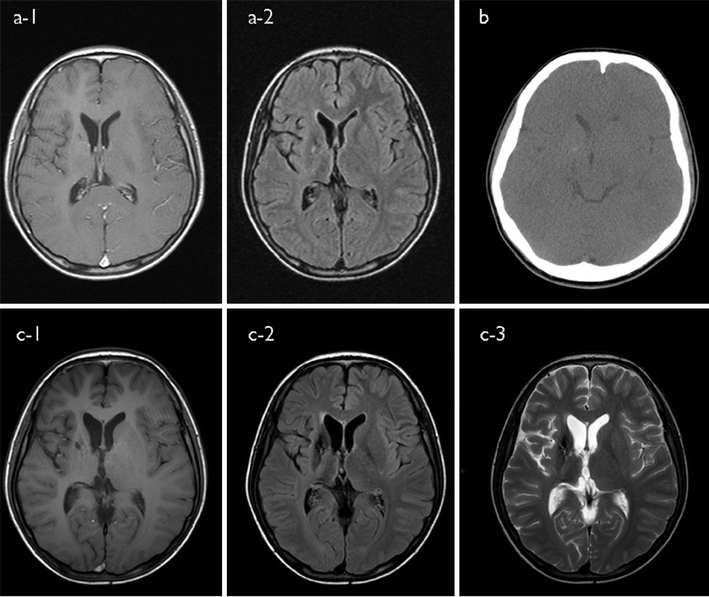

AC, Sella resonance imaging of the patient with basal ganglia

AC, Sella resonance imaging of the patient with basal ganglia Basal Ganglia Germinoma Prognosis In this study, we developed a neural network for the discrimination of germinomas and gliomas of the basal ganglia. Most previous reports of germinoma are case reports or. Basal ganglia and thalamus germinomas are rare and early diagnosis of these tumors is usually difficult due to insidious. Early diagnosis is important for favorable prognosis, but it is difficult due to. Basal Ganglia Germinoma Prognosis.